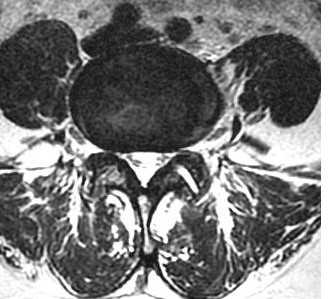

МРТ поясничного отдела позвоночника. Остеоартрит и остеоартроз дугоотростчатых суставов. Аксиальная Т2-взвешенная МРТ.

Остеоартроз приводит к уменьшению бокового кармана (в норме 5 мм на поясничном уровне). Синовиальная суставная жидкость может выходить через щели в капсуле сустава и осумковываться, образуя кисту. Типичное место расположения синовиальных кист – уровень диска L4-5. На КТ киста гипо- или гиперденсна, в ее стенке могут быть кальцинаты. При МРТ позвоночника синовиальная киста гипо- или слегка гиперинтенсивна на Т2-зависимых МРТ изображениях.

МРТ поясничного отдела позвоночника. Синовиальная киста справа. Аксиальная Т2-взвешенная МРТ.